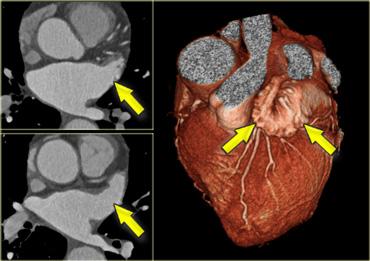

Tiểu nhĩ trái

Tiểu nhĩ trái là một cấu trúc dạng ngón tay có bè cơ, xuất phát từ phần trên bên của nhĩ trái. Nó nằm trên rãnh nhĩ thất trái và che phủ một phần động mạch vành trái trong đó.

Các bó cơ nhỏ chạy song song của nó không nên bị nhầm lẫn với huyết khối.

Tái tạo 3D cho thấy tiểu nhĩ trái (mũi tên xanh) và động mạch vành trái (mũi tên vàng) sau khi đã loại bỏ tiểu nhĩ trái. A=trước, S=trên

Khi đánh giá các động mạch vành, cần loại bỏ tiểu nhĩ trái để có thể quan sát được động mạch mũ trái (LCX) và đoạn gần của động mạch liên thất trước (LAD).